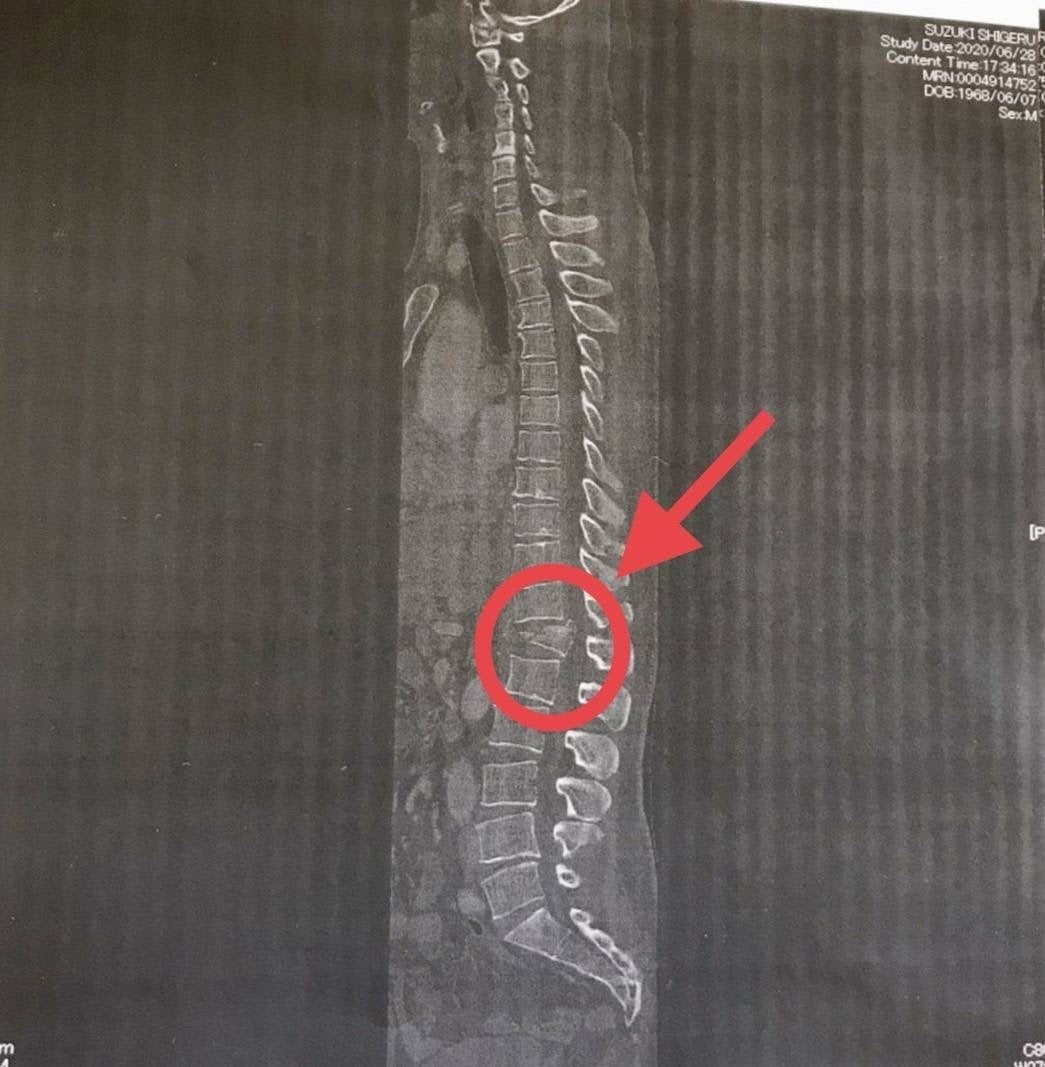

手術は無事終わり地獄のようなリハビリが開始され私生活にも支障が出るほどつらい毎日だった。実際のレントゲン写真が残っている。着地の衝撃で背骨が砕け押し出されているのがわかる。押し出された背骨が脊髄をさらに押し出し神経までも損傷した。